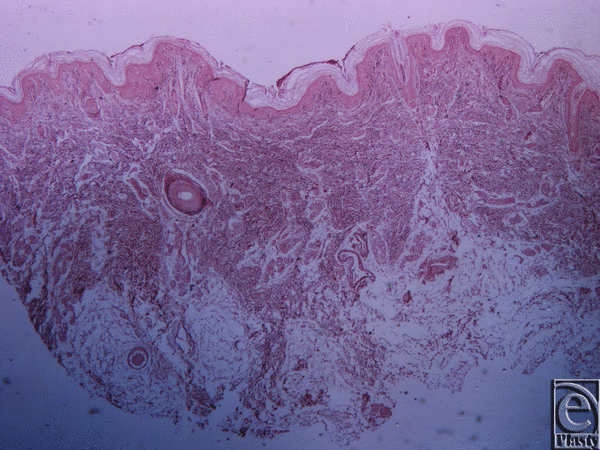

![]() |

| Figure 5. Inframammary crease. (a) Reticulin stain ×25. (b) Reticulin stain ×200. The collagen type III fibers are stained in black and radiate from the underlying muscle fascia. |

Microscopic evaluation of skin specimens revealed normal dermis and appendages in all cases. In all sections of the inframammary crease specimens, no breast parenchyma was present. In the subcutaneous tissue, there was a well-defined network of dense collagen fibers that create a beehive pattern of the subcutaneous fat (Fig 3). This pattern is denser in the deeper sites in relation to the fascia of the underlying muscle (Figs 4, 5a, and 5b). The collagen fibers network has a broad base of attachment to the dermis. In the sections from the medial sites of the crease, the beehive pattern has the same structure as that described earlier but appears looser. However, it becomes denser in the deeper sites. In the sections of the lateral sites of the crease, the beehive pattern is equally well organized, with broad base attachments of the collagen bundles to the dermis (Fig 6). In some of the cases, the bundles are thinner than those at the other sites. The elastic fibers participate in the formation of the collagen pattern and radiate in a relatively parallel pattern in the reticular dermis and in a perpendicular fashion in the papillary dermis (Fig 7).

The histological results of the specimens of the inframammary crease presented in this study are similar to the results of the previously described studies by Boutros et al3 and Lockwood.4 In the subcutaneous tissue, there is a well-defined network of dense collagen fibers that creates a beehive pattern network of the subcutaneous fat. This network is denser in deeper sites related to the pectoralis muscle fascia. The collagen fibers network has a broad base of attachments to the dermis. In the medial sites of the crease, the beehive pattern has the same structure as described earlier, only looser, which also becomes denser in the deeper sites. In the lateral sites of the crease, the beehive pattern network is just as well organized, with broad base attachments of the collagen bundles to the dermis. In some of the cases, the bundles are thinner than those at the other sites. The elastic fibers participate in the collagen pattern and radiate in a relatively parallel pattern in the reticular dermis and in a perpendicular fashion in the papillary dermis.